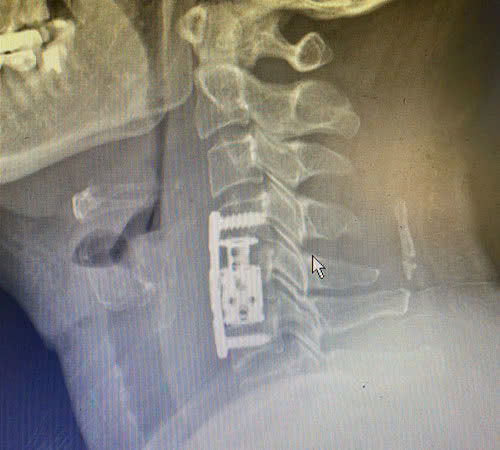

Đây là biểu hiện của hội chứng chèn ép tủy cổ gây ra. Trên phim chụp CT-Scanner, MRI cho thấy người bệnh bị thoát vị đốt sống cổ đoạn C4-C5, C5-C6, cốt hóa dây chằng dọc sau.

Sau khi hội chẩn và thống nhất, các bác sĩ tiến hành phẫu thuật thay thân đốt sống, lấy nhân đĩa đệm, đặt đốt sống nhân tạo đốt sống cổ, vít cố định đốt sống cổ cho người bệnh.

| Hình ảnh vùng đốt sống cổ của người bệnh sau khi được thay đốt sống cổ nhân tạo |